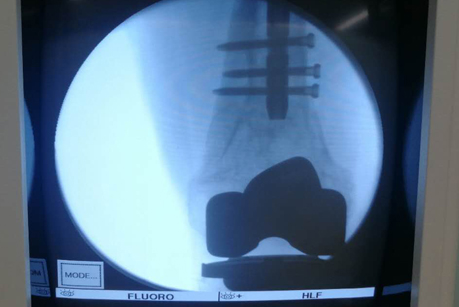

在手术之前,首先做股骨全长薄层扫描CT,将患者股骨影像及数据搜集并记录下来,通过3D打印技术制作出一个1:1比例的股骨“复制品”,它的直径、长短、髓腔形态都与患者真实情况完全相符,甚至患者骨骼上每一块凹陷与凸起,每一点纹理和痕迹都呈现得一清二楚。然后通过在体外对模型进行模拟手术操作,准确制订出了髓内钉的入针点、长度、直径,精确计划出远端锁钉准确位置。手术时,按着术前的设计顺利完成了手术,大大缩短了手术时间,减少了对患者的创伤。术后影像骨折解剖复位,锁钉位置精准无误,术后患者顺利康复。

术中影像

术后影像